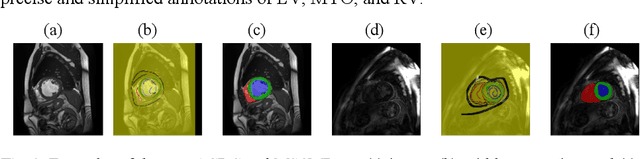

Abstract:Despite the recent progress in medical image segmentation with scribble-based annotations, the segmentation results of most models are still not ro-bust and generalizable enough in open environments. Evidential deep learn-ing (EDL) has recently been proposed as a promising solution to model predictive uncertainty and improve the reliability of medical image segmen-tation. However directly applying EDL to scribble-supervised medical im-age segmentation faces a tradeoff between accuracy and reliability. To ad-dress the challenge, we propose a novel framework called Dual-Branch Evi-dential Deep Learning (DuEDL). Firstly, the decoder of the segmentation network is changed to two different branches, and the evidence of the two branches is fused to generate high-quality pseudo-labels. Then the frame-work applies partial evidence loss and two-branch consistent loss for joint training of the model to adapt to the scribble supervision learning. The pro-posed method was tested on two cardiac datasets: ACDC and MSCMRseg. The results show that our method significantly enhances the reliability and generalization ability of the model without sacrificing accuracy, outper-forming state-of-the-art baselines. The code is available at https://github.com/Gardnery/DuEDL.